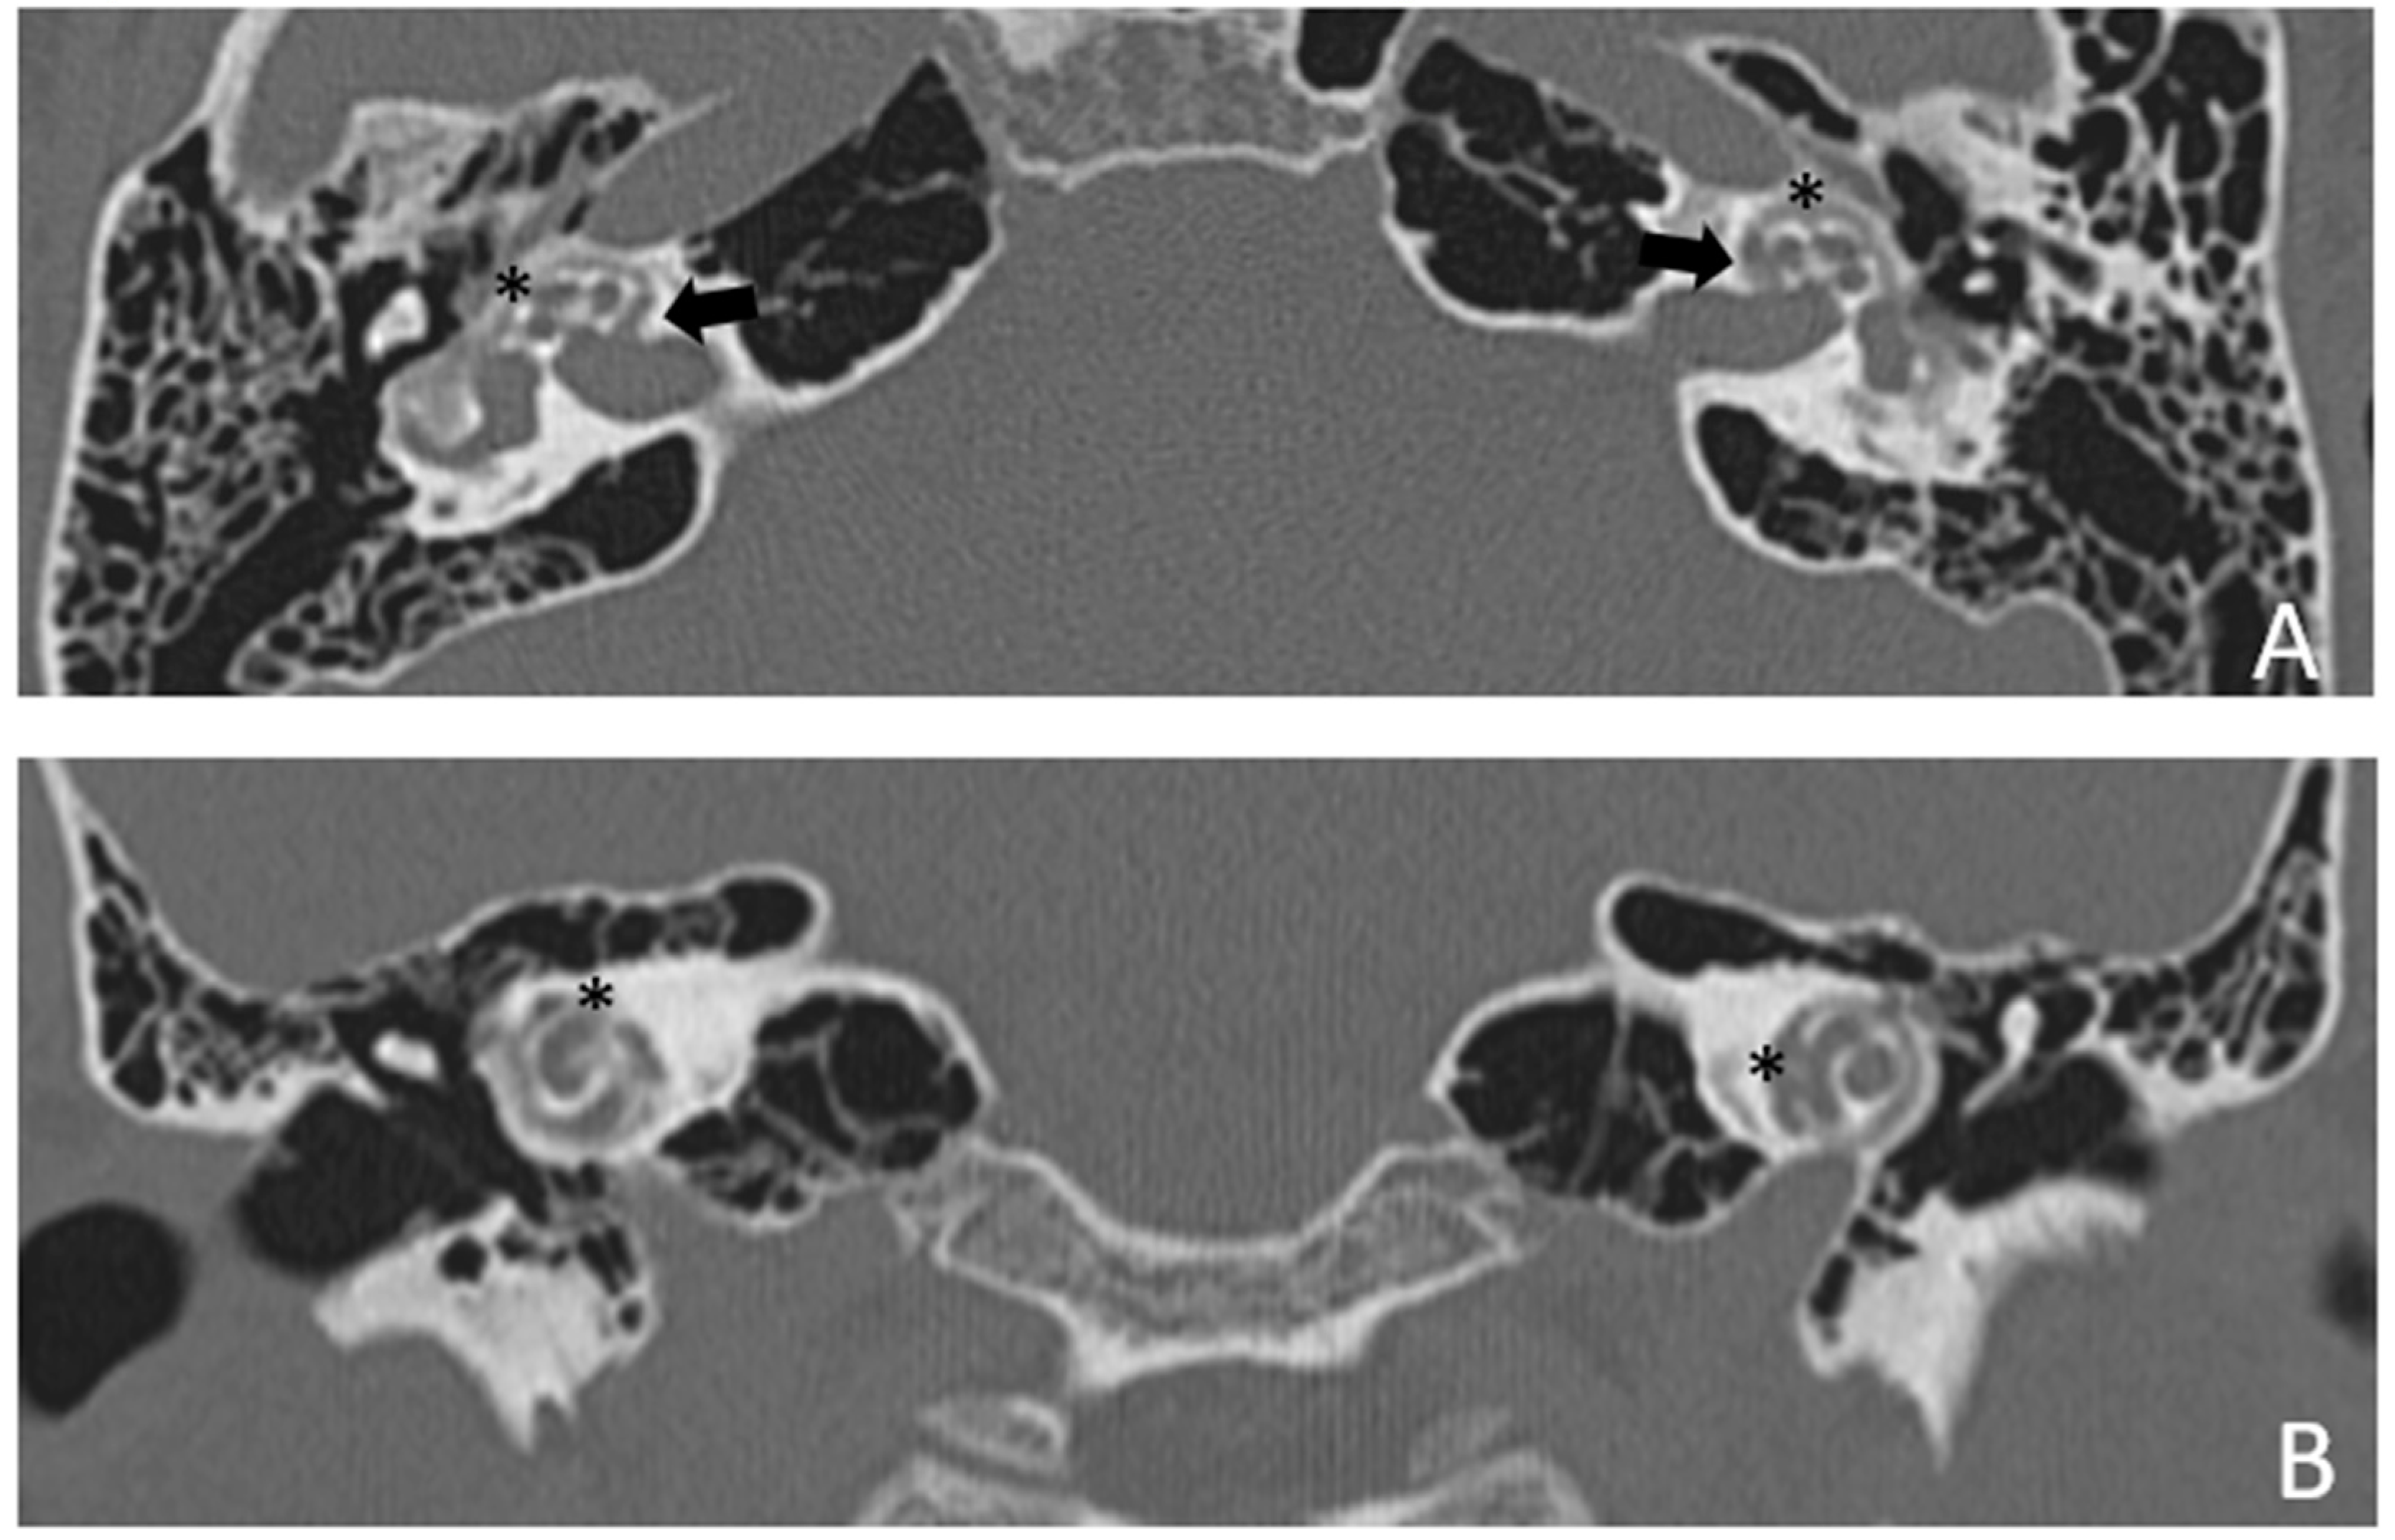

Figure 7. CT images of patient #4 with otosclerosis. A and B, axial plane. The cavity around the cochlea is clearly visible as well as the communication of the cavitating osteorarefation with the cochlea,marked with asterisks.